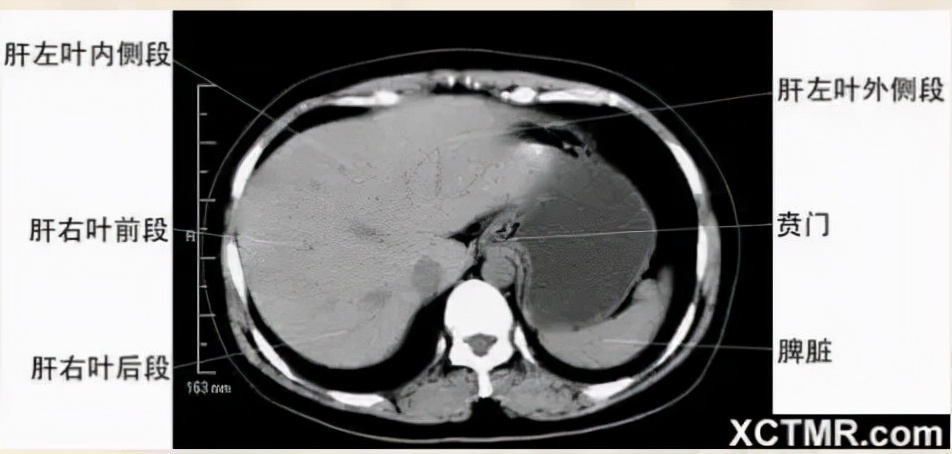

腹部CT